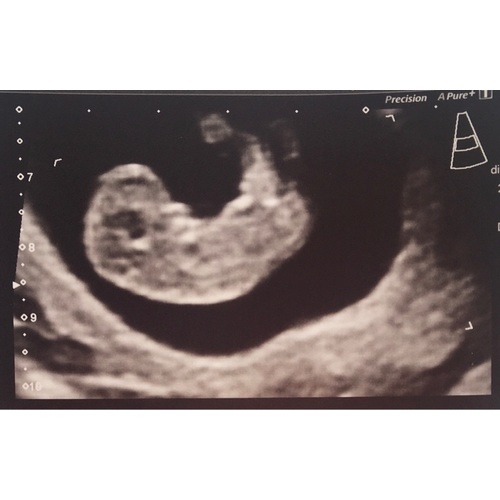

Bij 10+ 1 is de nekplooi nog niet goed te zien en zegt het niet zo veel. Als je gekozen hebt voor de combinatie test kijken ze er naar. Anders alleen als de afwijking echt opvalt. Dat is bij onze verloskundige zo. Paar dagen terug gezet geen probleem. Mogelijk ga je weer vooruit als je bij 12 weken een echo zou hebben! Bij 10 is het allemaal nog niet zo duidelijk. Komt goed! Mooie echo!!

Gisteren ook mijn termijnecho gehad en ook ik ben een paar dagen terug gezet. Volgens mij betekent dit niets ernstigs.

Tussen 10 en 12 wk is het meest betrouwbaar om het termijn vast te stellen, dus iets teruggezet worden is niet erg. Over nekplooi: is pas nauwkeurig vanaf 11 wk, kan zijn dat ze daarom niet specifiek naar heeft gekekenbof benoemd. Als het echt afwijkend had gekeken had je vk het wss wel gezegd en een extra echo ingepland een week later. Zou me daar nu niet druk om maken! Nekplooi wordt in nl niet meer standaard gemeten met 11/12 wk trouwens sinds de nipt er is